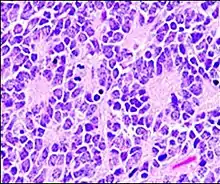

Perivascular pseudorosette

A perivascular pseudorosette consists of a spoke-wheel arrangement of cells with tapered cellular processes radiates around a wall of a centrally placed vessel. The modifier “pseudo” differentiates this pattern from the Homer Wright and Flexner-Wintersteiner rosettes, perhaps because the central structure is not actually formed by the tumor itself, but instead represents a native, non-neoplastic element. Also, some early investigators argued about the definition of a central lumen, choosing “pseudo” to indicate that the hub was not a true lumen but contained structures. Nevertheless, this pattern remains extremely diagnostically useful and the modifier unnecessarily leads to confusion. Perivascular pseudorosettes are encountered in most ependymomas regardless of grade or variant. As such, they are significantly more sensitive for the diagnosis of ependymomas than true ependymal rosettes. Unfortunately, perivascular pseudorosettes are also less specific in that they are also encountered in medulloblastomas, PNETs, central neurocytomas, and less often in glioblastomas, and a rare pediatric tumor, monomorphous pilomyxoid astrocytomas.[2]

Micrograph of perivascular pseudorosettes